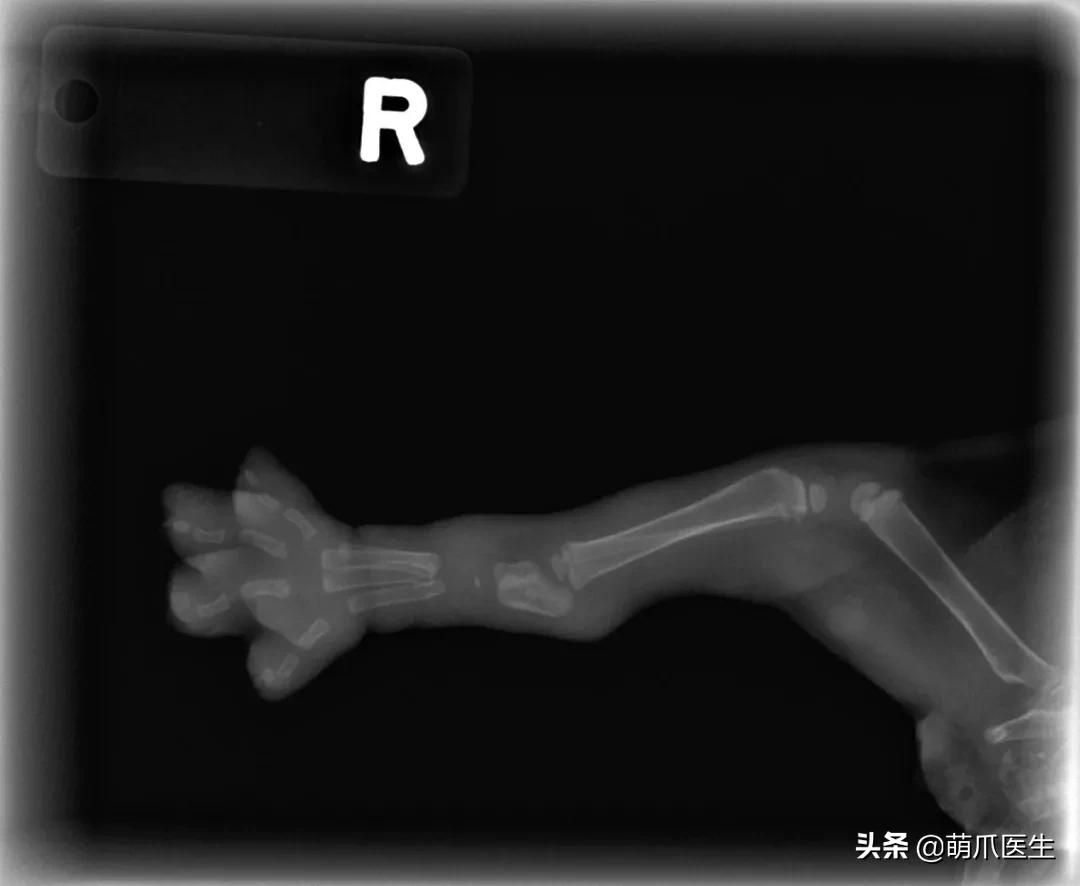

为了证明自己没有作假,LinzerBinzer不得不上传了小猫咪另一只脚的X光片,看上去确实是同样的效果……

小猫年龄只有5~6周大,骨骼系统还没有完全发育。此时它骨头之间相连的结缔组织在X射线下是透明的,所以看上去才会如此“不真实”。

网友提供了一只仅出生3天的狗狗X光片